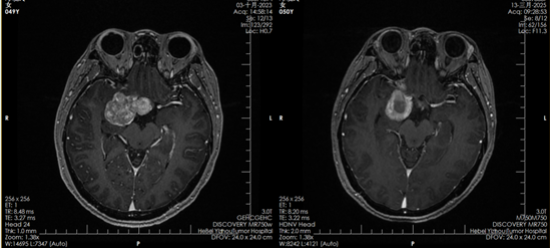

2023年10月,邓女士正式开始质子治疗。一个多月里,她接受了30次治疗。“治疗的时候一点感觉都没有,就像躺下来休息一会儿。要不是看到复查影像里的肿瘤变化,我都不敢相信这是真的。”邓女士说。

质子治疗前后对比影像

如今,复查影像显示肿瘤已被有效控制,她的坚持终于换来了可喜的结果。